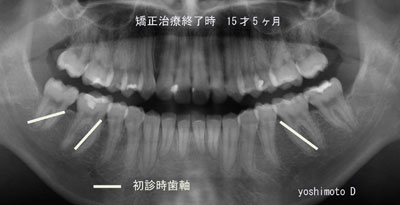

最終的にフルブラケットを各歯牙に装着し仕上げを行い矯正治療を終了します。牽引した左上の行い、矯正歯も正常並びレントゲンでもほぼ正常に機能出来るようになりました。通常なら4本の小臼歯を間引きする症例ですが当医院では非抜歯咬合誘導を行うことで下顎の臼歯部が整直し各歯牙の歯軸は平行性が保たれ、咬合力に強い症例と仕上げることが出来ました。歯槽膿漏・虫歯になりにくい咬み合わせで、この咬合を維持するようにメインテナンスを行う事で8020(80歳で20本の歯を残す)また、6024(60歳で24本歯を残す)が達成出来ます。

初診時年齢9歳3ヶ月、dental age IIIA, 21番の埋伏による11番の近心移動を認めるAngle classI症例です。

正貌は左右対称ですが、軽度の下口唇の肥厚を認めます。側貌は口元の突出感はなく、良好です。異常嚥下癖があります。

口腔内所見としては、over jet +2.7mm, over bite +3.1mm。12,42番の反対咬合、21番根尖相当部の歯肉の膨隆、下顎前歯部の叢生があります。側方歯群は乳歯が残存しています。

パントモより、上下顎第1大臼歯ならびに側方歯群永久歯胚の近心傾斜を認めます。

セファログラム分析から、convexityがほぼ+1S.D., A-B plane angleは-1S.D.を越えて小さく、Mandibular planeも-1S.D.で下顎に対して上顎がやや前方位、かつlow mandible の顔貌であることがわかりました。

小野の回帰方程式から、,下顎に-6mmのdiscrepancyを算出し、スライドに示すような診断となりました。

下顎には3Dリンガルアーチを適用して6番のアップライトと遠心移動をはかりました。その結果、大臼歯関係は一時的にII級となります。

その後、上顎には3Dクワドヘリックスを使用、前述のように6番の捻転を解消することによって大臼歯関係はI級になりました。クワドヘリックスを利用して近心移動した11番は遠心に移動し、21番のスペースを確保してから、21相当部を開窓、装置を装着して、エラスティックにより牽引し、歯列弓内にまで誘導してからDBSに上下顎の排列を行いました。

動的治療終了時、ならびに動的治療終了後2年の顔貌と口腔内写真を見ますと、安定した咬合が得られたことがわかります。

セファロトレースの重ね合わせと治療前後の分析も、良好な成長と側貌の改善が達成できたことを示しています。